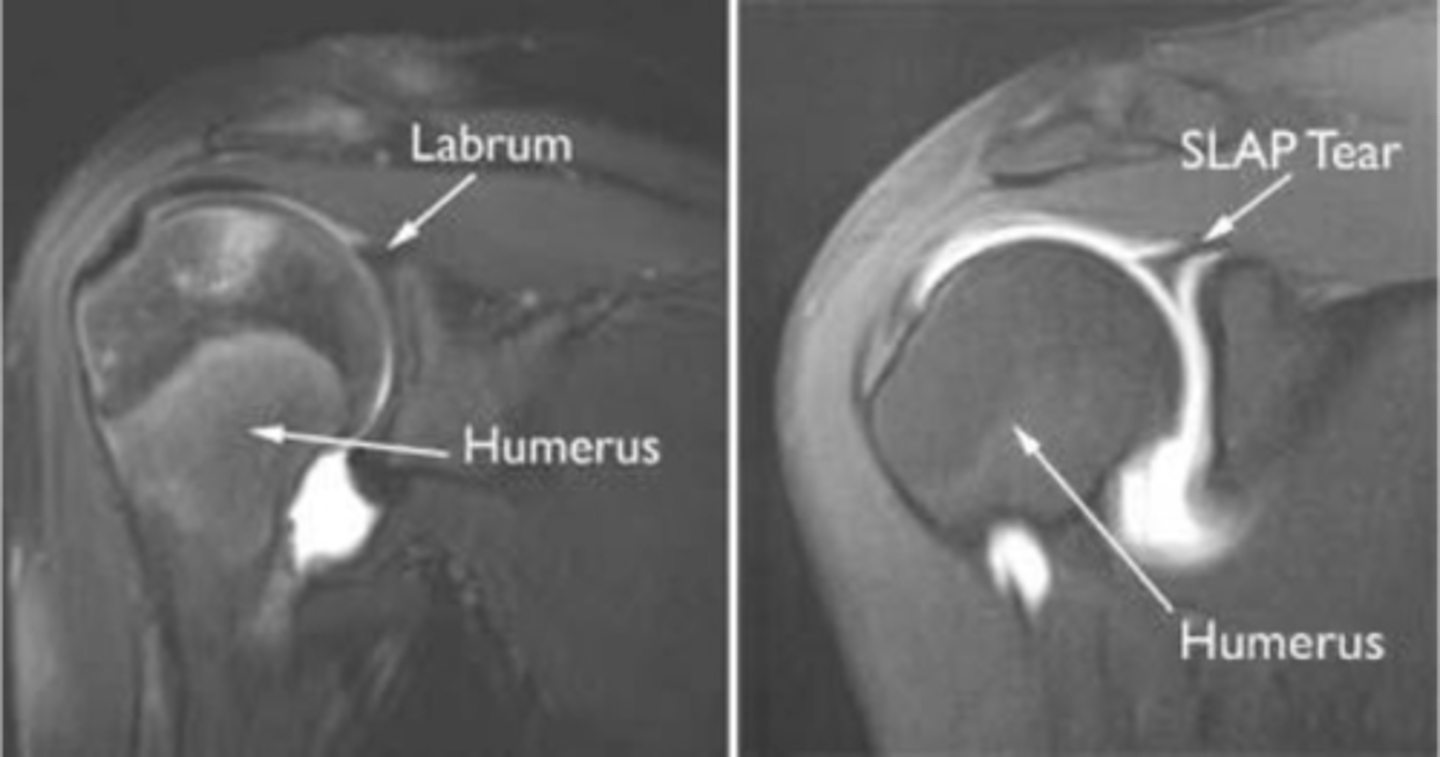

Labral tears -- dye is creeping into the labral region

What are these images depicting? How do you know?

1. When there is a labral tear, the dye will make its way into that region, as depicted in this image

2. ADHESIVE CAPSULITIS IS NOT PRESENT -- THIS IS A NORMAL PRESENTATION DUE TO THE DYE IN THE RECESS

Two questions for you on this one: why do we know there a labral pathology present? (1) and why is this NOT adhesive capsulitis? (2)